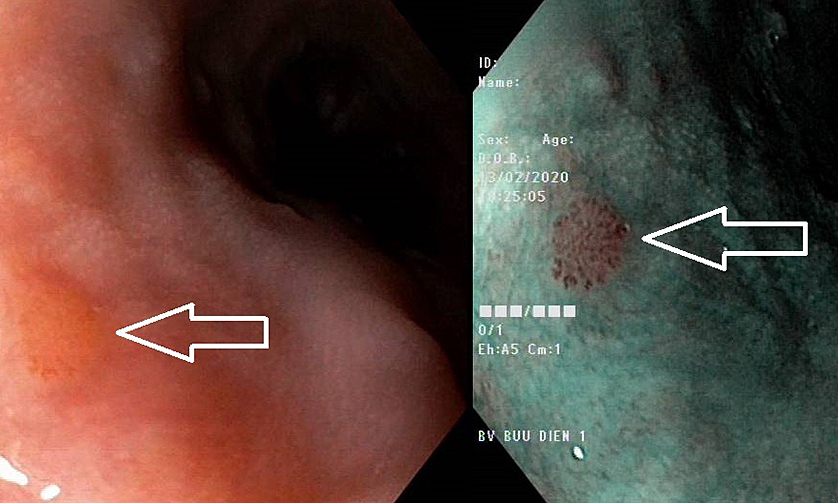

Hình ảnh nghi ngờ ung thư thực quản trên nội soi (khó quan sát) và nội soi NBI (nâu đen, hiệu chuẩn rõ). Ảnh: Cung cấp bởi bệnh viện-BS Nguyễn Văn Thịnh, Trưởng khoa nội soi nổ chức năng Bệnh viện Bưu điện cho biết, nguyên lý của phương pháp nội soi nhuộm dải hẹp NBI là thay dải ánh sáng trắng bình thường thành hai dải bước sóng ngắn hơn. Dải sáng ngắn này được hấp thụ bởi huyết sắc tố (hemoglobin) trong mạch máu. Nhờ đó, tăng độ tương phản giữa cấu trúc mao mạch và lớp biểu mô bề mặt, giúp bác sĩ có thể quan sát rõ cấu trúc mạch máu lớp bề mặt trong quá trình phẫu thuật. Kết hợp với độ phóng đại lên đến 100x, bác sĩ có thể quan sát được những tổn thương cực nhỏ chỉ 2mm.

Thông qua công nghệ này, các bác sĩ có thể đánh giá các bất thường về cấu trúc của bề mặt và mạch máu để phát hiện các bệnh ung thư tiền ung thư và ung thư. Giai đoạn đầu của thực quản, dạ dày và đại tràng, ở giai đoạn này, các tế bào ác tính chỉ nằm ở niêm mạc hoặc lớp dưới niêm mạc.